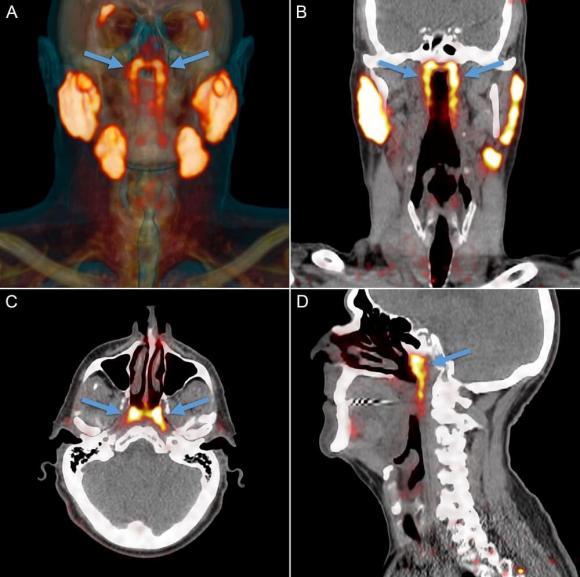

Theo PubMed, vào năm 2020, các nhà nghiên cứu Hà Lan công bố phát hiện một cặp tuyến nước bọt mới nằm ngay phía sau mũi, trong khu vực nối giữa khoang mũi và họng. Sau đó, nó đã được các chuyên gia đặt tên là tuyến nước bọt ống hầu (tubarial salivary glands). Phát hiện này lập tức làm dậy sóng truyền thông và cộng đồng khoa học vì nếu đúng, nó sẽ bổ sung vào "bản đồ" giải phẫu người vốn tự hào có 3 cặp tuyến nước bọt lớn đã được biết đến lâu nay.

Theo NKI, câu chuyện bắt đầu không phải từ phòng mổ giải phẫu mà từ… máy PET/CT cho bệnh nhân ung thư tiền liệt tuyến. Khi các bác sĩ tiêm chất đánh dấu và soi hình ảnh, họ thấy hai vùng sáng bất thường ở vòm họng xuất hiện nhất quán trong hàng loạt bệnh nhân đã gợi ý có một cấu trúc tuyến lớn hơn những "tuyến nhỏ rải rác" mà sách y đã mô tả trước đó. Khám nghiệm thêm trên xác và phân tích mô cho thấy tồn tại mô tuyến với nhiều ống dẫn, đủ để các tác giả đặt vấn đề đây là một "vùng tuyến" có thể coi là cơ quan.

Phát hiện có chiều hướng mang ý nghĩa lâm sàng rõ rệt: nếu tuyến này thực sự tồn tại và đóng góp vào việc giữ ẩm, bôi trơn vòm họng, thì trong xạ trị vùng đầu-cổ các bác sĩ cần tránh bắn quá mạnh vào khu vực này. Bằng chứng sơ bộ từ nhóm nghiên cứu cho thấy bệnh nhân chịu liều xạ cao ở vùng này thường gặp khô miệng, khó nuốt là những di chứng ảnh hưởng nghiêm trọng đến chất lượng sống. Vì vậy, "phát hiện tổn thương có thể tránh được" này được mô tả như một cơ hội để giảm tác dụng phụ của điều trị ung thư.